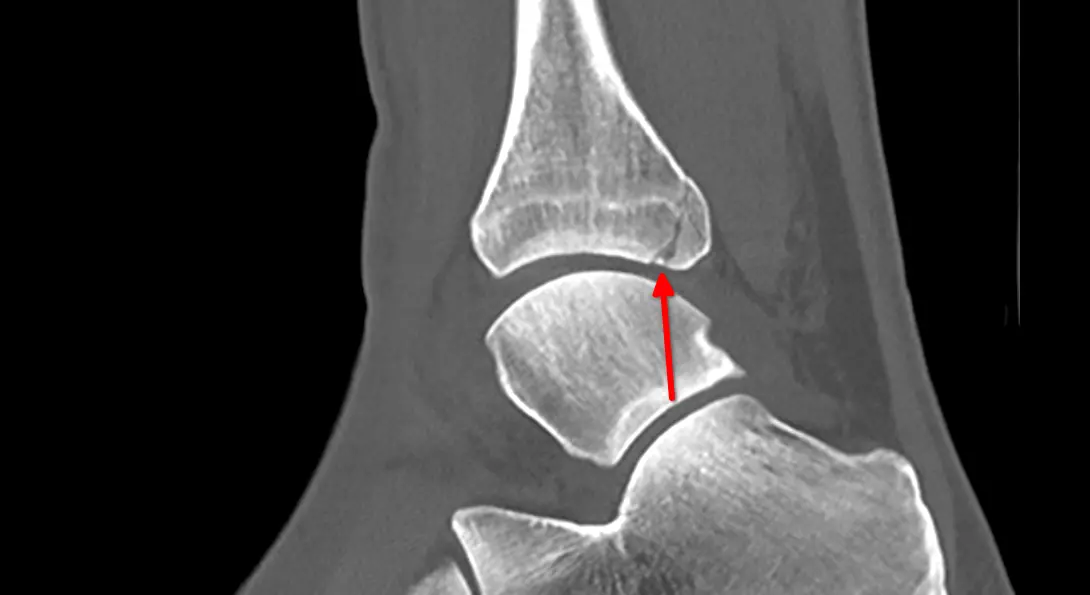

Zum Glück legte meine Freundin bei ihrem Hausarzt ein gutes Wort für mich ein. Also ging es am Montag zunächst in die Praxis, dann zur Radiologie: erst Röntgen, zurück zur Praxis, anschließend noch einmal zum CT. Die ersten Befunde ließen nichts Gutes erahnen, von einem leichten Bruch war die Rede.

Der Arzt organisierte schließlich einen Termin in der Unfallchirurgie im Krankenhaus. Eine Stunde später saß ich dort, erneut beim Röntgen. Und siehe da: Auch das Wadenbein hatte einen Knacks.

Das Gesundheitssystem funktioniert, das ist die gute Nachricht. Am Ende wurde mir schnell und effektiv geholfen. CT-Aufnahmen und andere Bilder wurden digital sofort übertragen und waren sowohl im Krankenhaus als auch beim Arzt unmittelbar verfügbar.

Eine kleine Randnotiz aus Aktionärssicht: Viele der Geräte im Einsatz stammten von Siemens Healthineers. Auf der diesjährigen Hauptversammlung wurde ja bereits angekündigt, dass Aktionäre zusätzliche Aktien erhalten sollen. Schon beeindruckend, was diese Geräte heute alles leisten können.